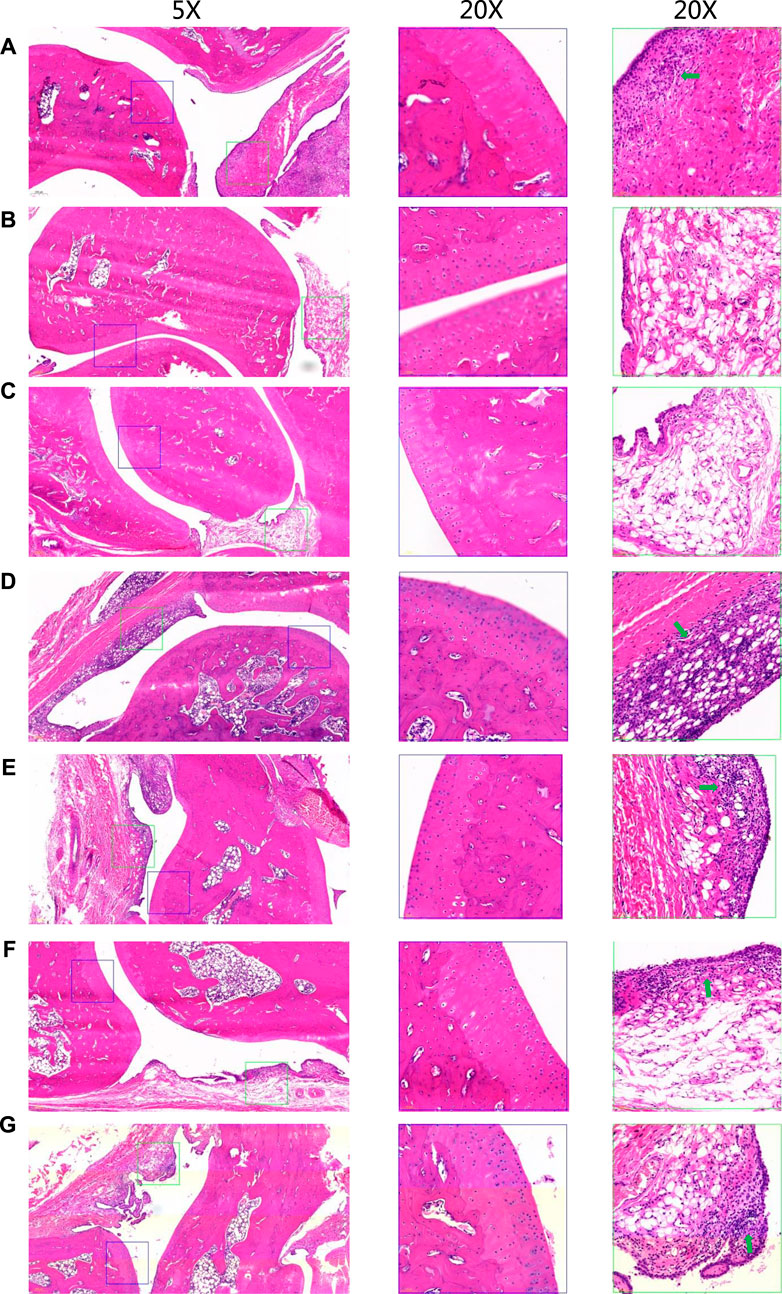

为评估STE的抗炎效果,研究采用了ELISA和免疫组织化学分析方法。ELISA检测结果显示,相较于正常大鼠,模型组胶原蛋白诱导性关节炎(CIA)大鼠血清中的白细胞介素-1β(IL-1β)和白细胞介素-6(IL-6)水平显著上升。与模型组相比,经STE和双氯芬酸处理后,上述细胞因子水平有所下降。特别是1.35 g/kg剂量的STE对IL-1β和IL-6水平的影响尤为显著。在组织病理学方面,与正常大鼠的踝关节相比,CIA大鼠的踝关节显示出明显的病理变化,包括软骨侵蚀、滑膜内层增生、滑膜细胞层排列紊乱以及周围组织中单核细胞的大量浸润(图3A、B)。经STE治疗后,大鼠的组织病理学病变在不同程度上有所改善(图3C-G),这表明STE具有免疫抑制作用,能够对抗CIA大鼠的病理损伤。综上所述,与CIA大鼠相比,给予1.35 g/kg剂量STE的大鼠在所有病理损伤方面均显示出显著的减少。

图3 不同组别大鼠踝关节的代表性HE染色切片